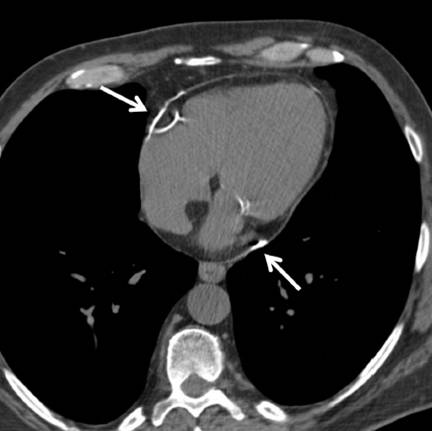

on contrast-enhanced CT enhancement of both outer

parietal and inner visceral layers of the pericardium due to inflammation (white arrow) with interposed mild effusion.

CT(非增强)Nongated unenhanced cardiac CT demonstrates

only minimal thickening of the pericardium up to 3 mm but presence

of linear pericardial calcification (white arrows) over the

right and left atrioventricular grooves suggestive of prior pericardial

process.